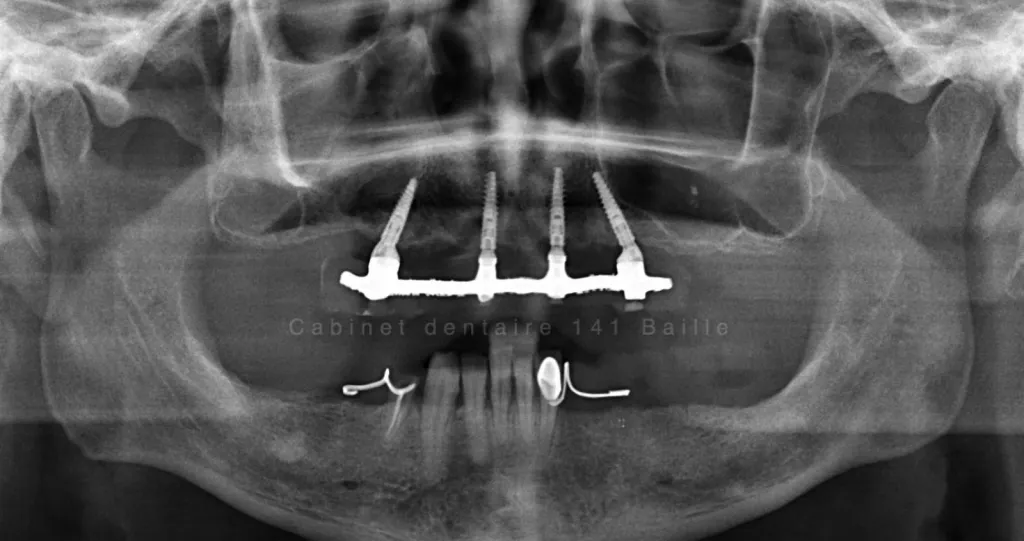

all on 6 chirurgie guidée par spécialiste all on 6 implantologie dentaire

Chirurgie implantaire guidée : l’expertise d’un spécialiste en implantologie à Marseille pour les techniques All-on-4 et All-on-6

Spécialiste implantologie à Marseille, expert All-on-4 et All-on-6. Découvrez comment la chirurgie implantaire guidée offre précision, sécurité et résultats immédiats.